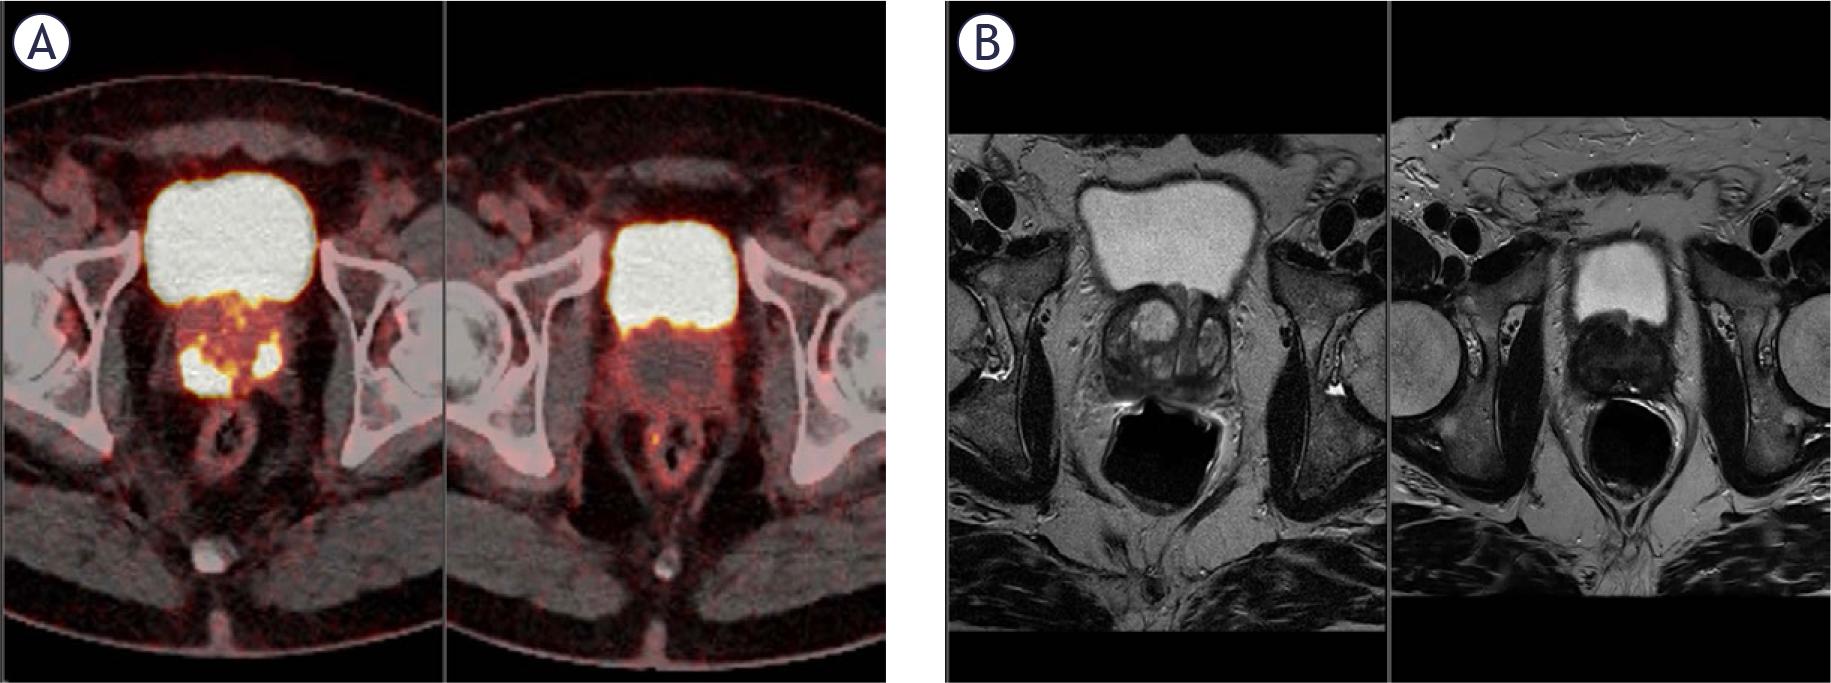

FIGURE 2.